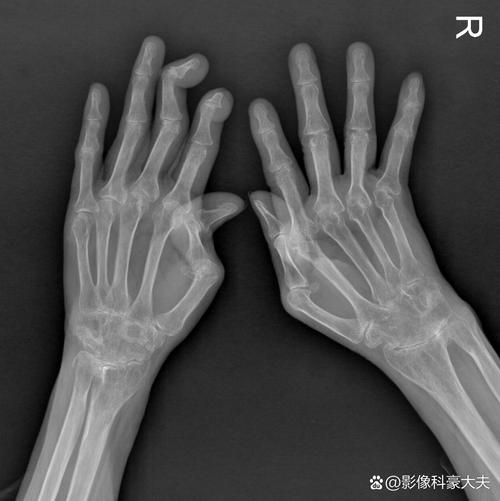

骨侵蚀

(图片来源网络,侵删)- 虽然X光片也能发现骨侵蚀,但MRI能更早、更清晰地发现这些微小的骨质破坏,它不仅能看到骨皮质的缺损,还能评估侵蚀灶周围的炎症情况。